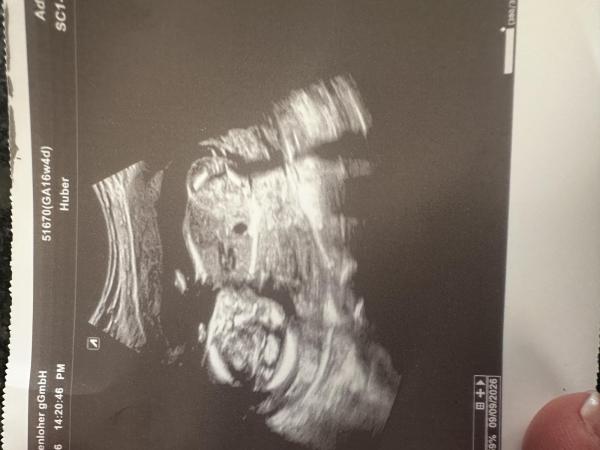

Was sagt ihr?

Bild zu Mädchen oder Junge 17ssw - Schwanger - wer noch? Rund um die Schwangerschaft

Aus der Position sieht man das Geschlecht nicht

Hallo, ich kann mit " Andocken spreiz Haltung" leider nichts anfangen und erkenne nichts auf diesem Bild. Warte besser noch ab bis zum nächsten Ultraschall und vertraue lieber der Aussage Deines Arztes, bevor Du von Laien zutreffende Aussagen erhofft. Alles Gute weiterhin für Deine Schwangerschaft.